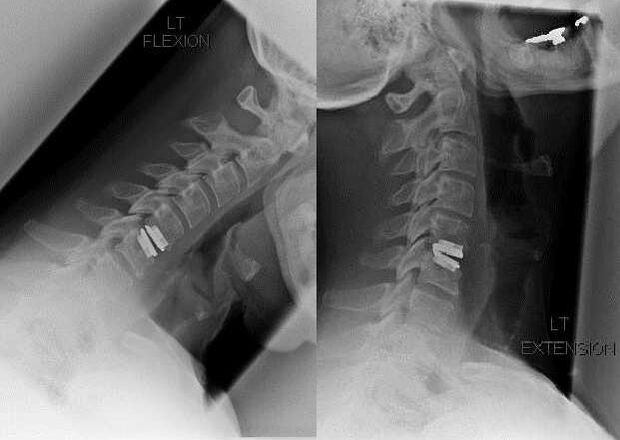

Interwencja chirurgiczna

Wskazania do interwencji chirurgicznej obejmują nieskuteczność leczenia zachowawczego, a także powikłania osteochondrozy szyjnej, na przykład dyskogenną mielopatię, zespół tętnicy kręgowej i zespół korzeniowy. Aby odbarczyć rdzeń kręgowy, naczynia krwionośne i korzenie kręgosłupa, wykonuje się następujące operacje:

- laminektomia;

- laminotomia;

- foraminotomia;

- facetektomia;

- dyskektomia.

Podczas operacji można wyciąć fragmenty kości i więzadeł, a także całkowicie lub częściowo usunąć krążki międzykręgowe. W przypadku małych wypukłości przepukliny często wykonuje się laserową waporyzację jądra krążka międzykręgowego.

Po wycięciu struktur kręgowych często wymagana jest stabilizacja segmentów ruchowych kręgosłupa poprzez zespolenie kręgosłupa lub założenie autoprzeszczepów kostnych i skórnych.